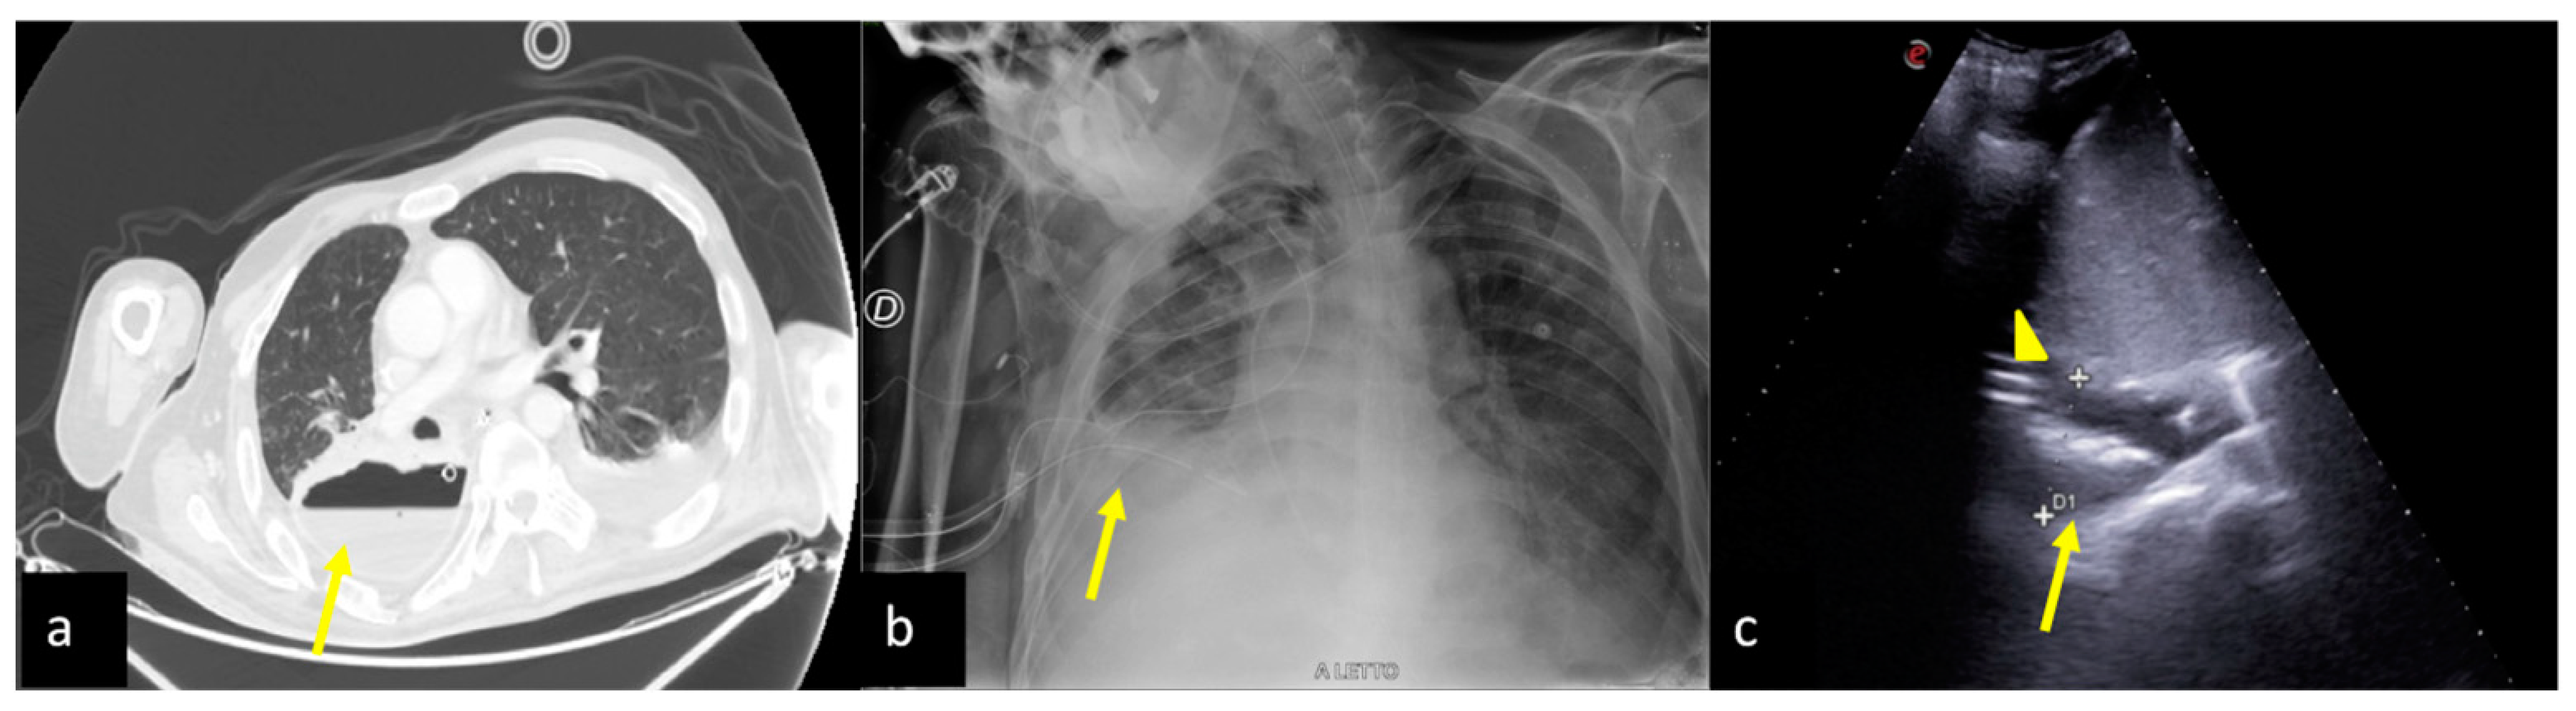

2.6. Pulmonary Contusion

3. Confirming or Excluding Pneumothorax and Monitoring its Evolution

4. Checking and Monitoring the Devices